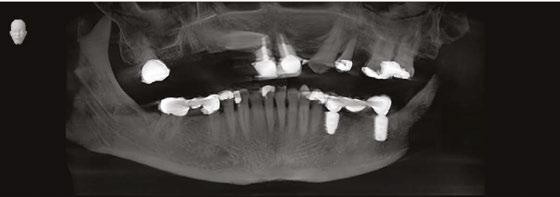

This is the presentation of the restoration of a 78-year-old male with multiple complicating factors.

Mr. Z has a skeletal Class III malocclusion. He has never received orthodontic treatment. The CBCT shows tooth No. 6 is present but horizontally impacted (Figure 4).

Based on age of patient, health history, and presence of the impacted canine, the patient was sent to an oral surgeon for evaluation. The initial consultation asked the surgeon to consider removal of impacted tooth No. 6 and placement of bone graft as a prelude to restoring site 2-7 with an implant-supported fixed bridge (Figures

Close inspection of the CBCT shows tooth No. 6 is ankylosed. The oral surgeon indicated extraction of tooth No. 6 would require block resection of bone with the tooth. The resulting defect would have required extensive bone grafting

added time and cost to this case.

5 and 6). and Douglas D. Wright, DDS, is a general dentist in private practice in Staunton, Virginia. William T. Goodwin II, DDS, is a maxillofacial surgeon in private practice in Harrisonburg, Virginia. For questions about this article, please contact Dr. Wright at dominosign14@ gmail.com. Figure 1: Pretreatment photo of patient. Note the extreme wear of mandibular incisors occurring from uncorrected malocclusion. Also note the contact between tooth Nos. 9 and 22 when the mandible moves to the right. This “canine guidance” was incorporated into the fixed-bridge design on the patient’s upper right side Figures 2 and 3: Metal framework at try-in appointment. Porcelain-fused-tometal was used to restore this case because of lack of interarch space

On the day of surgery, the patient had MegaGen AnyRidge® implants placed at the following sites under local anesthesia:

• Tooth No. 7: trans-canine placement of 4.0 mm x 13 mm

• Tooth No. 3: 5.0 mm x 7.0 mm with small crestal approach sinus graft

• Tooth No. 13: 4.0 mm x 10.0 mm implant

Retaining tooth No. 6 and placing the dental implant through the impacted and ankylosed tooth provided a new set of challenges. Keeping the ankylosed canine in place reduced the need for additional surgery; however, with the retention of the canine, insufficient interarch space would be available for a zirconia or resin-composite restoration. Because the interarch space was limited, a porcelainfused-to-metal restoration was used to complete the case.

Figures 7 and 8: Healing abutments in place Figure 4: Pretreatment panoramic x-ray. Note position of maxillary right canine Figures 5 and 6: Pretreatment CBCT scan with treatment planning software. Virtual implant placement at site 10 shows thin buccal bone. Buccal bone graft was provided at time of surgery Figures 9 and 10: Porcelain-on-metal framework ready for delivery

2. Paton G, Fuss J, Goss AN. The transmandibular implant: a 5- and 15-year single-center study. J Oral Maxillofac Figure 14. Post implant placement. This CBCT shows implant at site 10 through the impacted canine. Implant at site 3 was placed right against the sinus floor Figures 13A and 13B: 13A. Trans-mandibular dental implants. 13B. Subperiosteal implants Figure 11: Surgical site on day of surgery Figure 12: Implant placement of tooth No. 7 with buccal bone graft